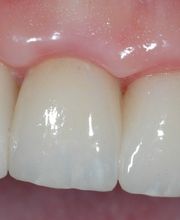

Das Bodensee Implantat Zentrum (ZIP) ist Ihre führende Praxis für Zahnheilkunde in der Region. Wir sind spezialisiert auf hochwertige Implantologie, einschliesslich des All-on-4® Konzepts, für das wir als Excellence Center Gold-zertifiziert sind. Unser Leistungsspektrum umfasst Komplettsanierungen, Kronen, Brücken sowie ästhetische Behandlungen. Mit über 30 Jahren Erfahrung bieten wir auch Angstpatienten eine einfühlsame Betreuung und Behandlungen unter Narkose für ein strahlendes Lächeln.